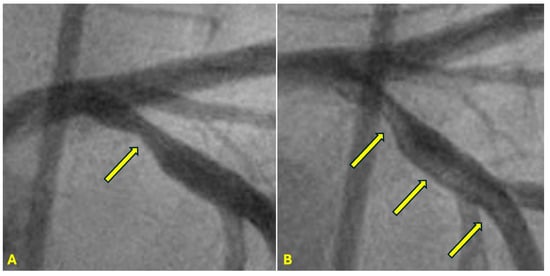

Figure 2. The left anterior descending (LAD) artery exhibits severe narrowing in its proximal segment (indicated by an arrow), while the right coronary artery (RCA) demonstrates a subtotal lesion in its mid-segment. Current angiographic techniques capture these lesions but fail to provide critical insights into their formation mechanisms or potential progression over time. (A) The lesion in the proximal LAD has a characteristic “rat tail” appearance—featuring progressively severe narrowing in the distal direction. (B) The mid-RCA lesion has a “reversed rat tail” pattern, characterized by more severe narrowing proximally and a gradual reduction in severity distally. WHY?

CLINICAL APPLICATIONS Differences in Management between Systolic versus Diastolic Hypertension. In patients with uncontrolled high diastolic BP, the damage occurs in the antegrade direction due to rapid coronary antegrade flow during diastole. Under these conditions, the injury typically originates at the distal segment of the artery and gradually diminishes in severity toward the proximal segment, producing a lesion with a standard rat-tail configuration (Figure 22A).

In patients with uncontrolled systolic blood pressure (BP), damage to the coronary artery arises from an abrupt water hammer effect, which generates a retrograde pressure wave. This retrograde wave leads to a collision with the antegrade flow at the transition from diastole to systole. This results in a lesion characterized by a reverse rat-tail configuration (Figure 22B). To provide personalized medicine, the patient of Figure 22A needs to control diastolic BP, while the patient in Figure 22B needs to have systolic BP under near perfect control [40].